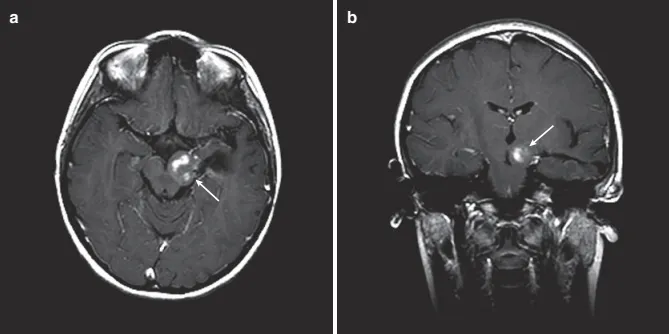

一位儿童脑桥胶质瘤的术后。该病例使用左侧颞中回入路,在颞部开颅手术后切除病灶。神经导航用于识别肿瘤的边界及关键神经组织定位,用穿孔锥来减少病灶体积。(a) 轴位 T1增强 MRI 显示肿瘤的轨迹及占据左侧被盖的肿瘤小残留。(b)冠状位增强 MRI,描绘了从颞中回通向中脑的肿瘤轨迹和小残留。该患者后续进行了化疗,不需要再次手术。没有新的神经功能缺损,但术后2周出现短暂性语言障碍。